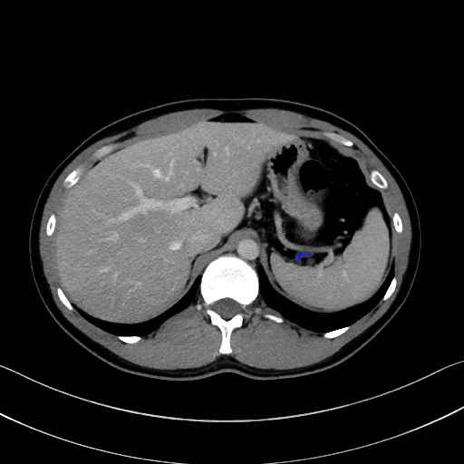

脾静脈の画像解剖

■起始:脾門で脾静脈枝が合流して本幹を形成。

■走行:膵体尾部の後面溝を右走し、膵頸部の後方で上腸間膜静脈(SMV)と合流して門脈を形成。

■主な流入枝:短胃静脈・左胃大網静脈・膵静脈、そして下腸間膜静脈(IMV)(変異あり)。